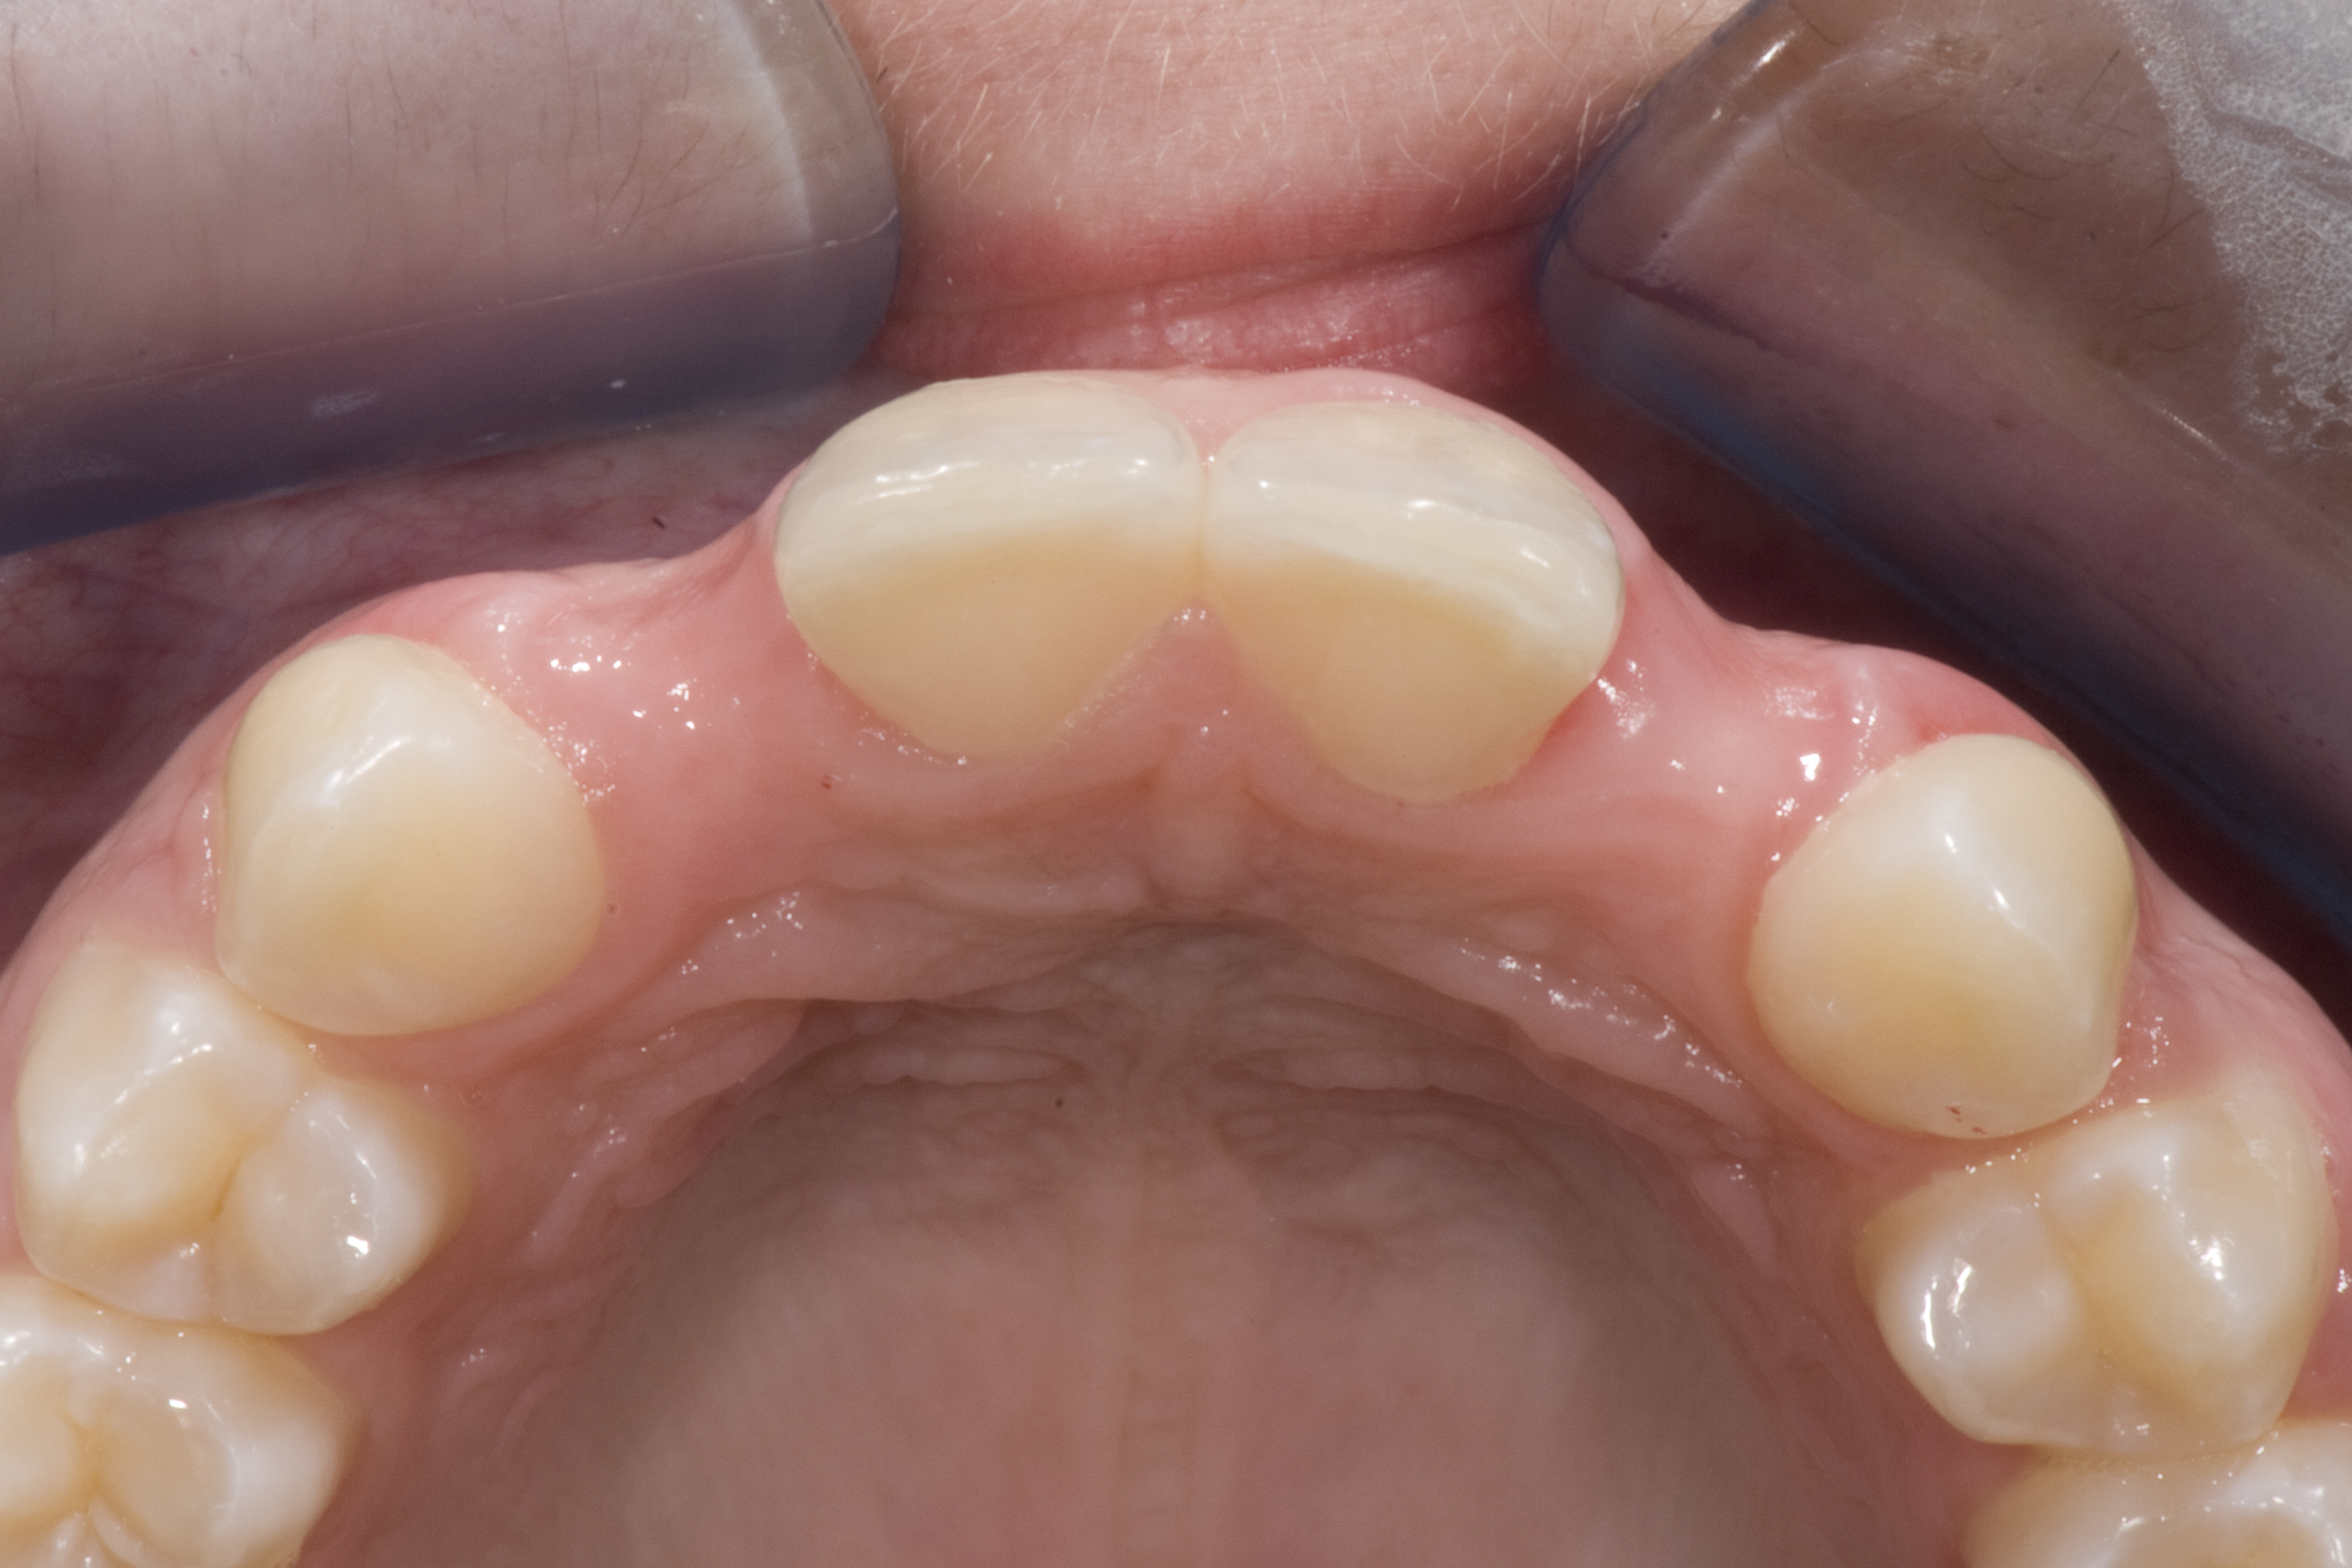

(14.) Occlusal view. Some form of augmentation would be needed if implants were being considered.

Figure 14

(24.) Occlusal view.

Figure 24